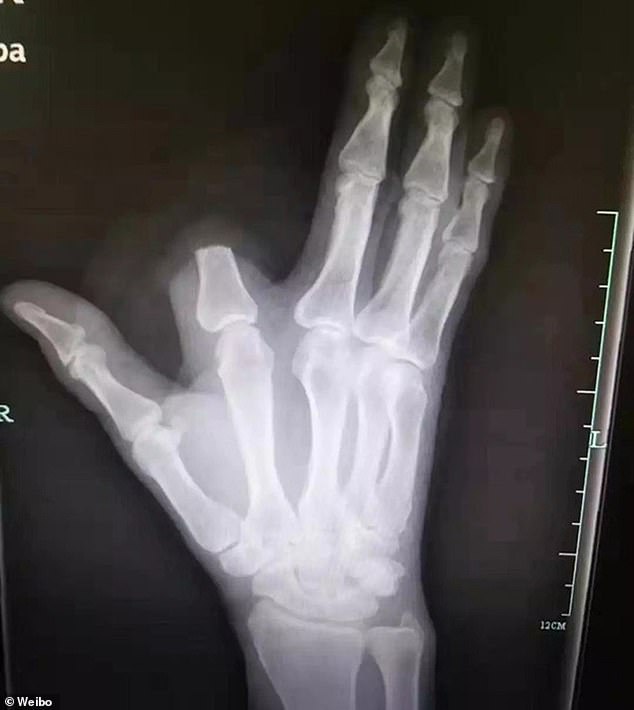

Ο 60χρονος αγρότης που το μικρό του όνομα είναι Γιανγκ, δούλευε στα χωράφια του αμέριμνος. Κάποια στιγμή ένιωσε κάτι να αγγίζει το πόδι του και μόλις έσκυψε είδε μια οχιά. Δεν πρόλαβε να αντιδράσει και το φίδι με μια αστραπιαία κίνηση του δάγκωσε το δάχτυλο του χεριού. Ο δείκτης του δεξιού του χεριού, πρήστηκε αμέσως και οι πόνοι ήταν φρικτοί.

Τότε ο αγρότης έκανε κάτι αψυχολόγητο. Έβαλε το δάχτυλο του σε μια πλατιά πέτρα και με έναν μπαλτά με μια κίνηση το έκοψε.

Το έδεσε όπως όπως και ξεκίνησε για το πλησιέστερο νοσοκομείο ΧανγκΖου για να τον περιθάλψουν ή και να καταφέρουν να επανακολλήσουν το μέλος του.

Τότε και μόνο, διαπίστωσε πως είχε παρατήσει το κομμένου του δάχτυλο επάνω στην πέτρα και δεν μπορούσε να το δώσει στους γιατρούς για να το επανακολλήσουν.